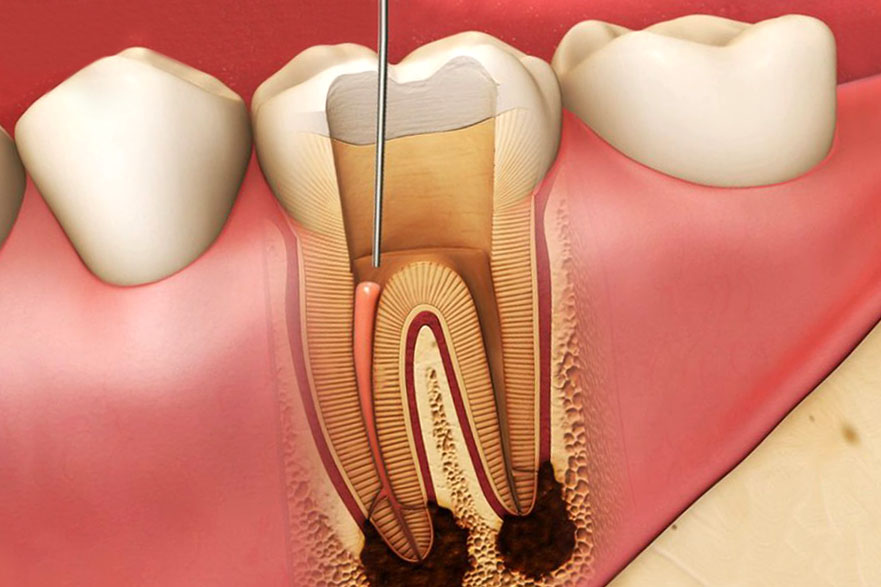

Реплантация зуба: Этапы и особенности операции